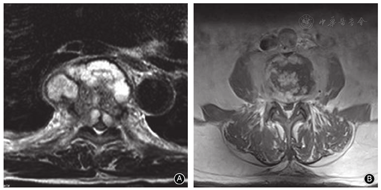

椎间盘脓肿形成强烈提示化脓性脊柱炎,MR增强扫描可见椎间盘周围的强化表现[16](图6)。64%的化脓性脊柱炎患者出现上述表现,而结核患者比例为9%[9]。椎体内脓肿形成并出现周围强化提示为脊柱结核,文献报道79%结核患者出现椎体内脓肿,而化脓性脊柱炎几乎为零[9]。结核和化脓性炎症均可导致椎旁脓肿和硬膜外脓肿,但发生率存在争议。Kim等[7]认为结核和化脓性炎症出现脓肿的比例类似;而Chang等[9]认为结核比化脓性炎症更容易出现椎旁脓肿(82% vs. 30%)和硬膜外脓肿(91% vs. 62%)。我们认为结核患者出现上述两个部位脓肿的比例更高,脓肿体积更大,可跨越病椎向上、下延伸。此外,我们还发现结核形成的脓肿经MR增强扫描,显示脓肿壁光滑且很薄;而化脓性炎症的脓肿壁往往较厚且边界不清(图7)。此与文献报道相一致[15,17]。

关节突关节周围出现异常高信号提示化脓性脊柱炎。文献报道57.8%的化脓性脊柱炎患者出现关节突关节周围高信号,而结核患者比例为零[15]。此外,在脊柱感染性疾病中累及椎弓根、椎板和棘突的比例很少(3%~12%);而一旦受到累及,则往往提示为脊柱结核,主要原因是结核杆菌更容易造成骨质破坏。此外,结核较化脓性脊柱炎更容易出现椎旁钙化表现,比例分别为65%和17%[9,15]。这与我们的经验一致,即临床上陈旧性结核患者经常可见椎旁出现明显的钙化或骨桥。